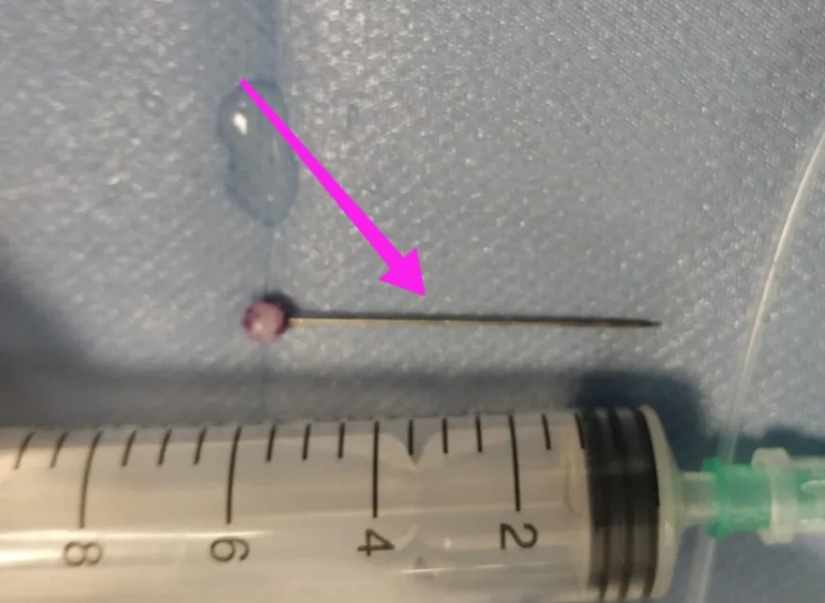

Η ανήλικη υπεβλήθη σε βρογχοσκόπηση και διαπιστώθηκε η μετακίνηση και ενσφήνωση της καρφίτσας στον δεξιό κύριο βρόγχο. Μετά οπό εργώδεις προσπάθειες ολοκληρώθηκε με επιτυχία η αφαίρεσή της.

Κατά την βρογχοσκόπηση διαπιστώθηκε η μετακίνηση και ενσφήνωση του ξένου σώματος στον δεξιό κύριο βρόγχο. Μετά οπό εργώδεις προσπάθειες ολοκληρώθηκε με επιτυχία η αφαίρεση αυτού. Η ασθενής ανένηψε πλήρως εντός της χειρουργικής αίθουσας. Η ασθενής μεταφέρθηκε για παρακολούθηση και νοσηλεία στη Γ’ Παιδιατρική Κλινική.